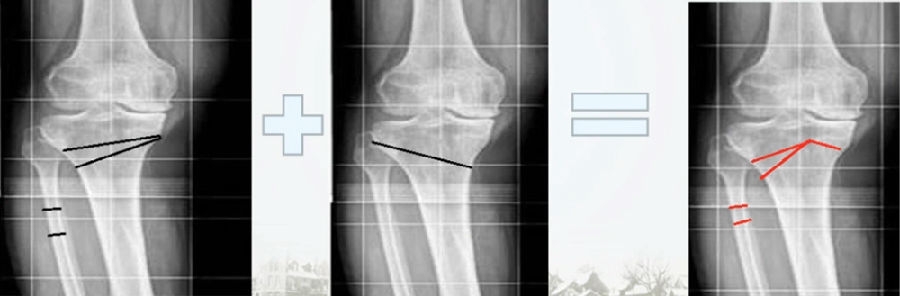

(1)OWHTO可分为上行性或下行性两种截骨方式。

(2)上行性OWHTO可降低髌骨高度的2%-11%;当髌骨高度下降10%,可引起髌股关节压力改变,引发膝前痛。

OWHTO上行截骨与下行截骨

(3)下行性OWHTO对髌骨高度影响较小。

(4)术前存在低位髌骨、髌股关节炎或内翻矫正度数较大时可考虑下行性OWHTO。

有文献证实下行截骨对髌骨的高度确实没有明显影响。

OWHTO下行截骨对髌骨的影响

第一次为该患者做了传统上行开放截骨,撑开角度较大,术后用三种方法测量髌骨高度,发现髌骨高度受到影响,髌骨变低了。

左膝上行OWHTO(初次)

上行OWHTO髌骨高度测量

ISI法测量髌骨无明显变化;CDI、BPI法测量髌骨降低明显;患者屈膝锻炼困难。

第二次来院做另一侧肢体时,采用下行截骨,术后患者髌骨高度,无论用哪种方法测量都无明显变化,而且患者膝关节功能迅速得到恢复。

右膝下行OWHTO(再次)

下行OWHTO髌骨高度测量

ISI法测量髌骨无明显变化;CDI、BPI法测量髌骨无明显变化;患者屈膝明显改善。